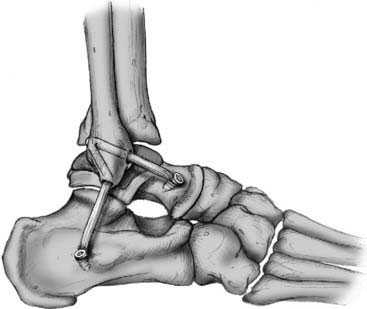

Артроскопическая реконструкция связок может проводиться либо с применением собственных связок пациента, либо с помощью трансплантатов с использованием специальных фиксаторов. Полностью разорванные связки не сшивают, а заменяют на новые. Трансплантат, заменяющий естественные связки, изготавливается из сухожилий полусухожильной мышцы (либо других) и фиксируется, либо с помощью рассасывающихся винтов, либо с помощью специальных титановых пуговиц.

Схематическое изображение операций.